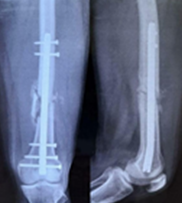

Distal Dilemma: Antegrade or Retrograde Nailing in Distal Femur Shaft Fractures

Ismail Pandor , Alim Shaikh , Abhishek Sharma , Aamir Shahzad , Fahim Ali , Anshuraj Jagdale